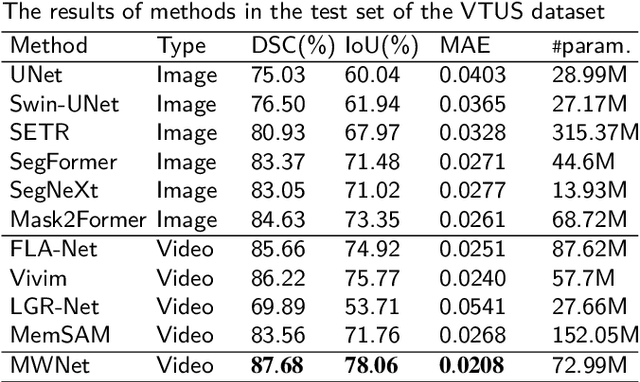

Abstract:Medical ultrasound videos are widely used for medical inspections, disease diagnosis and surgical planning. High-fidelity lesion area and target organ segmentation constitutes a key component of the computer-assisted surgery workflow. The low contrast levels and noisy backgrounds of ultrasound videos cause missegmentation of organ boundary, which may lead to small object losses and increase boundary segmentation errors. Object tracking in long videos also remains a significant research challenge. To overcome these challenges, we propose a memory bank-based wavelet filtering and fusion network, which adopts an encoder-decoder structure to effectively extract fine-grained detailed spatial features and integrate high-frequency (HF) information. Specifically, memory-based wavelet convolution is presented to simultaneously capture category, detailed information and utilize adjacent information in the encoder. Cascaded wavelet compression is used to fuse multiscale frequency-domain features and expand the receptive field within each convolutional layer. A long short-term memory bank using cross-attention and memory compression mechanisms is designed to track objects in long video. To fully utilize the boundary-sensitive HF details of feature maps, an HF-aware feature fusion module is designed via adaptive wavelet filters in the decoder. In extensive benchmark tests conducted on four ultrasound video datasets (two thyroid nodule, the thyroid gland, the heart datasets) compared with the state-of-the-art methods, our method demonstrates marked improvements in segmentation metrics. In particular, our method can more accurately segment small thyroid nodules, demonstrating its effectiveness for cases involving small ultrasound objects in long video. The code is available at https://github.com/XiAooZ/MWNet.

Abstract:Complicated image registration is a key issue in medical image analysis, and deep learning-based methods have achieved better results than traditional methods. The methods include ConvNet-based and Transformer-based methods. Although ConvNets can effectively utilize local information to reduce redundancy via small neighborhood convolution, the limited receptive field results in the inability to capture global dependencies. Transformers can establish long-distance dependencies via a self-attention mechanism; however, the intense calculation of the relationships among all tokens leads to high redundancy. We propose a novel unsupervised image registration method named the unified Transformer and superresolution (UTSRMorph) network, which can enhance feature representation learning in the encoder and generate detailed displacement fields in the decoder to overcome these problems. We first propose a fusion attention block to integrate the advantages of ConvNets and Transformers, which inserts a ConvNet-based channel attention module into a multihead self-attention module. The overlapping attention block, a novel cross-attention method, uses overlapping windows to obtain abundant correlations with match information of a pair of images. Then, the blocks are flexibly stacked into a new powerful encoder. The decoder generation process of a high-resolution deformation displacement field from low-resolution features is considered as a superresolution process. Specifically, the superresolution module was employed to replace interpolation upsampling, which can overcome feature degradation. UTSRMorph was compared to state-of-the-art registration methods in the 3D brain MR (OASIS, IXI) and MR-CT datasets. The qualitative and quantitative results indicate that UTSRMorph achieves relatively better performance. The code and datasets are publicly available at https://github.com/Runshi-Zhang/UTSRMorph.